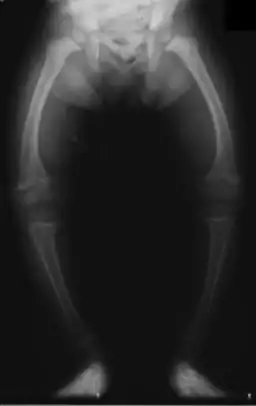

Primidone, along with phenytoin and phenobarbital, is one of the anticonvulsants most heavily associated with bone diseases such as osteoporosis, osteopenia (which can precede osteoporosis), osteomalacia and fractures.[29][30][31] The populations usually said to be most at risk are institutionalized people, postmenopausal women, older men, people taking more than one anticonvulsant, and children, who are also at risk of rickets.[29] However, it has been suggested that bone demineralization is most pronounced in young people (25–44 years of age)[30] and one 1987 study of institutionalized people found that the rate of osteomalacia in the ones taking anticonvulsants—one out of nineteen individuals taking an anticonvulsant (vs. none among the thirty-seven people taking none) —was similar to that expected in elderly people. The authors speculated that this was due to improvements in diet, sun exposure and exercise in response to earlier findings, and/or that this was because it was sunnier in London than in the Northern European countries which had earlier reported this effect.[31] In any case, the use of more than one anticonvulsant has been associated with an increased prevalence of bone disease in institutionalized epilepsy patients versus institutionalized people who did not have epilepsy. Likewise, postmenopausal women taking anticonvulsants have a greater risk of fracture than their drug-naive counterparts.[29]

Anticonvulsants affect the bones in many ways. They cause hypophosphatemia, hypocalcemia, low Vitamin D levels, and increased parathyroid hormone. Anticonvulsants also contribute to the increased rate of fractures by causing somnolence, ataxia, and tremor which would cause gait disturbance, further increasing the risk of fractures on top of the increase due to seizures and the restrictions on activity placed on epileptic people. Increased fracture rate has also been reported for carbamazepine, valproate and clonazepam. The risk of fractures is higher for people taking enzyme-inducing anticonvulsants than for people taking non-enzyme-inducing anticonvulsants.[30] In addition to all of the above, primidone can cause arthralgia.[22]